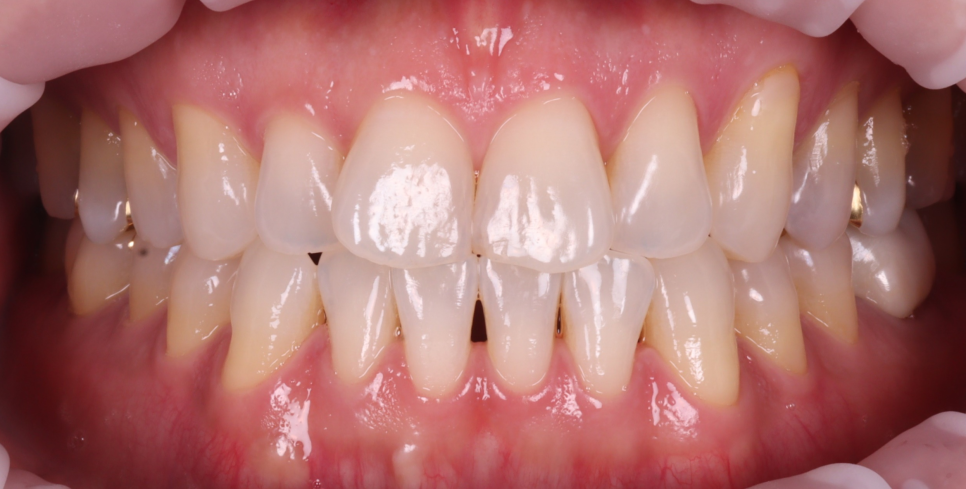

첫 만남부터 ‘신호’는 있었어요.

처음 오셨을 때는 타 치과에서

하신 골드 인레이가 떨어져 재부착을 도와드렸어요.

불편한 곳만 치료를 원하시는 경우에도

저는 전체적으로 검진을 해드리는데요.

촬영 : 240708

위 사진처럼 충치가 진행되고 있었고,

치료를 권해드렸으나

6개월 뒤에 하시겠다며 귀가하셨어요.